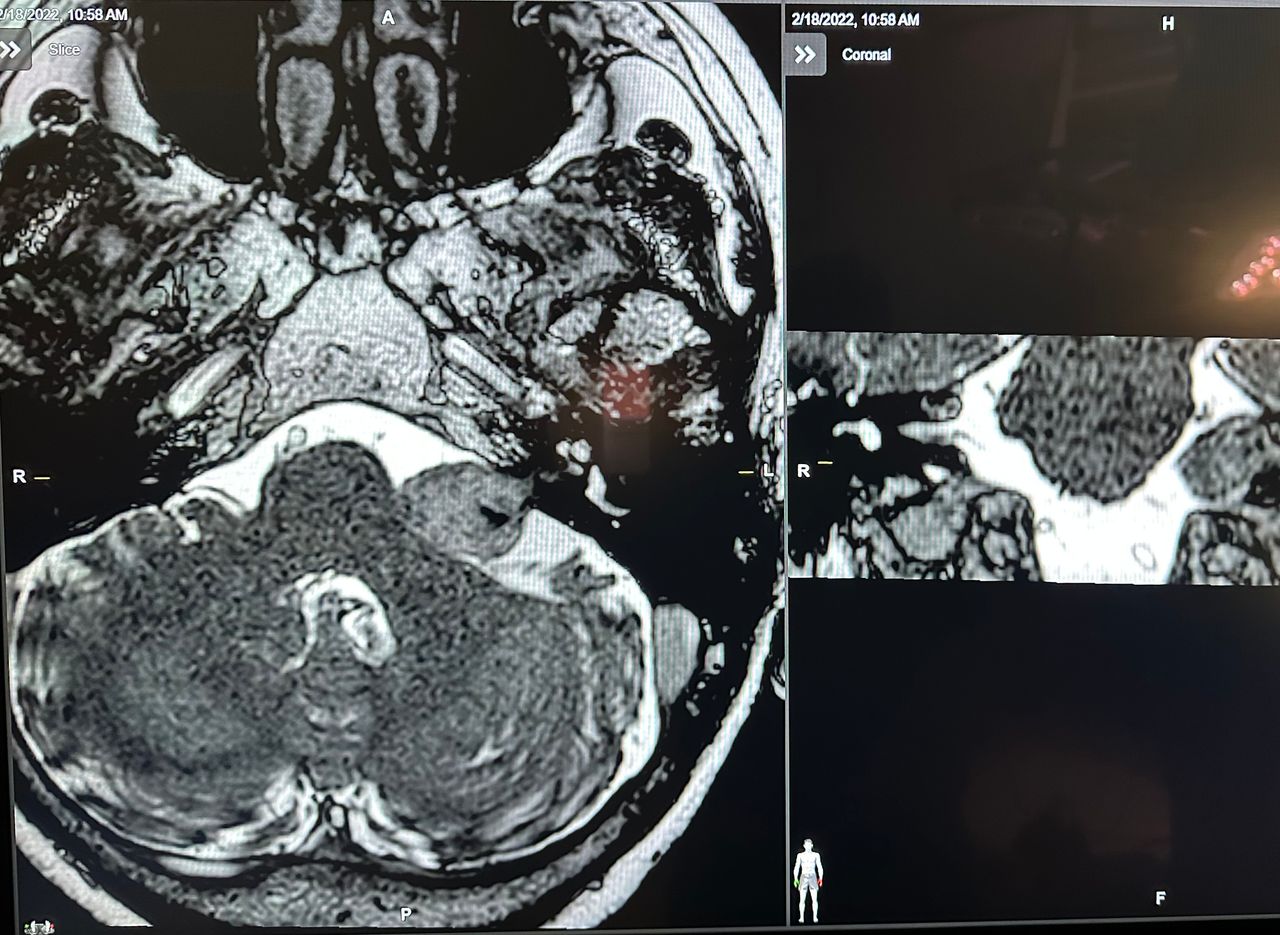

- Microchirurgia cerebrale: tumori (Meningiomi, gliomi, neurinomi ecc.) e malformazioni vascolari (Aneurismi, MAV, angiomi cavernosi, FAVD)